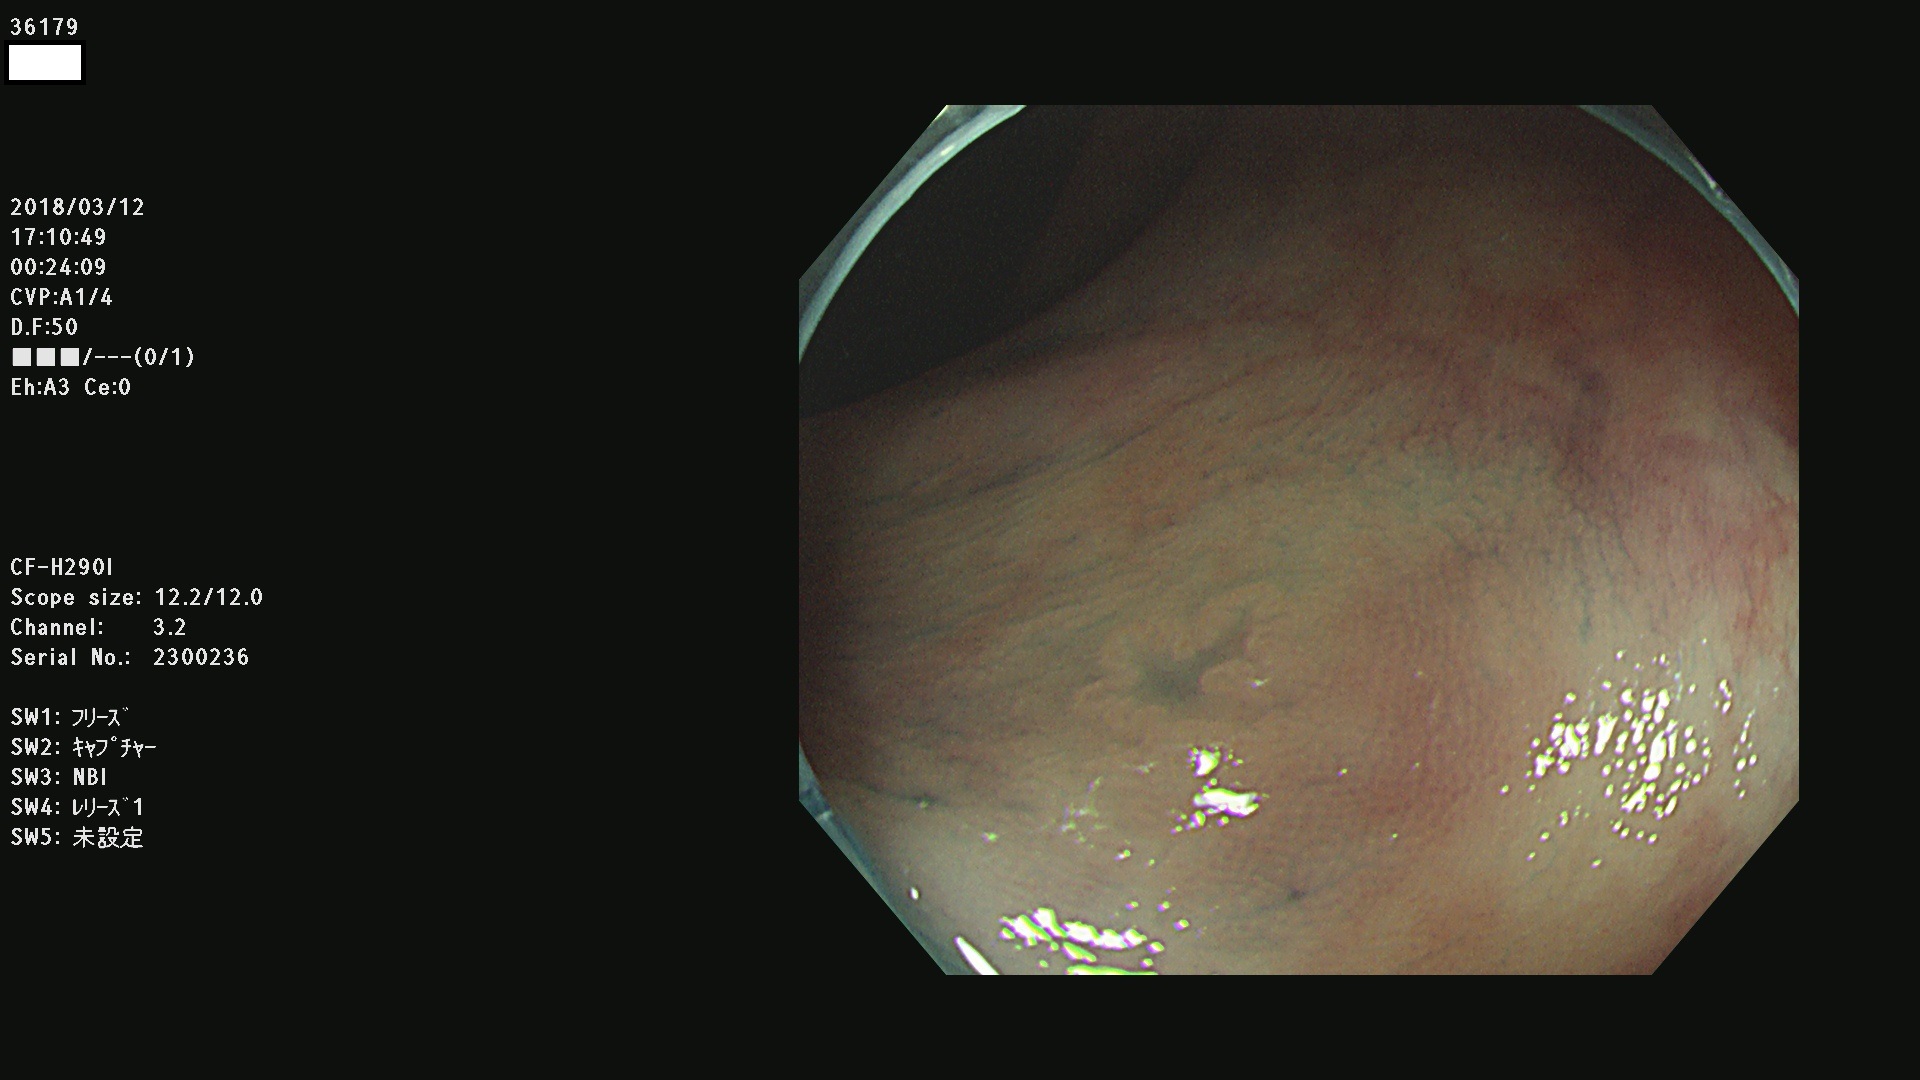

腺腫発見率57 % (カルテ番号 36100〜36199の100名の方の検査結果で集計)大腸癌検診最新情報

以下のカルテ番号の方に腺腫(Adenoma,Group3〜5)が見つかりました(集計法)

36100 36101 36102 36103 36104 36105 36107 36108 36110 36111 36114 36115 36117 36119 36120 36122 36125 36127 36129(SSA/Pのみ) 36133 36135 36137 36138 36139 36143 36144 36146 36147 36152 36153 36154 36155 36157(SSA/Pのみ) 36158 36162 36163 36165 36167 36169 36170 36173 36174 36176 36177 36178 36179 36180 36183 36185 36187 36189 36190(SSA/Pのみ) 36191 36193 36195(SSA/Pのみ) 36197(SSA/Pのみ) 36199(SSA/Pのみ)

発見困難で危険性の高い平坦型病変(上記100名より抽出) ![]()